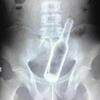

Mulher passa por cirurgia após ficar com vibrador de 20 cm preso no reto

Uma norte-americana que mora em Alabama, nos EUA, e diz ter ficado viciada em masturbação desde que terminou com o namorado, há três anos, contou ao programa “Stuck”, do canal britânico Quest Red, uma história que deixou os telespectadores impressionadores: ela foi levada ao hospital e precisou passar por uma cirurgia após ficar com um vibrador de 20 centímetros preso no reto. As informações são do Hugo Gloss.

O médico que a atendeu disse ter ficado bastante surpreso com o caso, mas explicou como o acidente aconteceu. “O reto é projetado para manter as fezes fora da região do ânus. Se alguém colocar algo mais além dessa parte, será sugado em direção ao intestino”, revela.